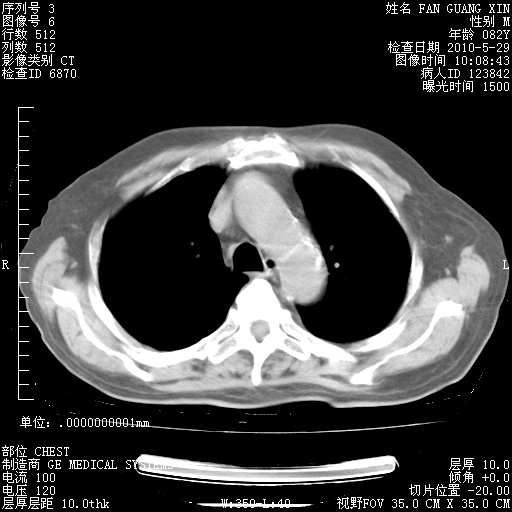

治疗3周后的肺部CT纵隔窗

再治疗10天后的肺部CT 纵膈窗